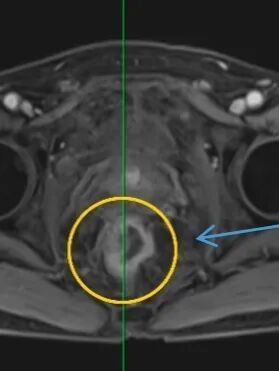

因便血入院时,老张并未意识到问题的严重性。然而,胃镜、肠镜、增强CT……一系列检查后,诊断结果如晴天霹雳:直肠中段腺癌;更令人倒吸一口凉气的是,检查竟意外发现老张的腹主动脉存在孤立性夹层,且直径已超过5厘米。

直肠中段腺癌

主动脉夹层